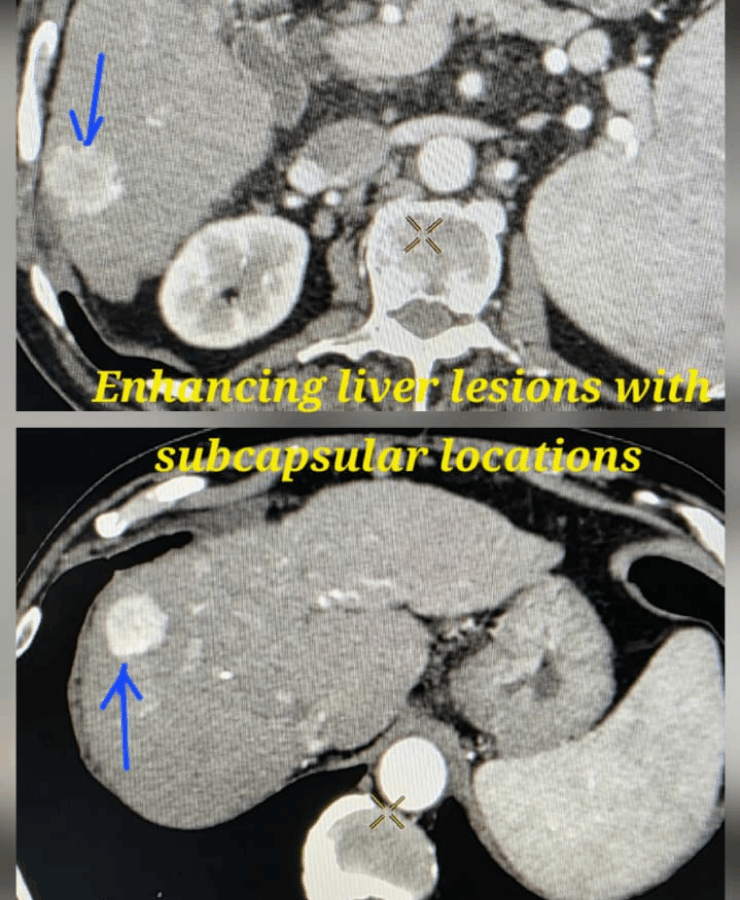

Liver Cancer Treatment

Many liver cancer patients are not suitable for surgery because of tumour location, multiple lesions, underlying liver disease or general health. In such cases, interventional radiological procedures can offer effective, targeted options:

- Thermal ablation (radiofrequency or microwave): destroys tumour tissue by heating it from within through a thin needle placed under USG/CT guidance.

- Chemoembolization (TACE): delivers chemotherapy directly into the tumour’s blood supply, followed by embolic particles to block the vessels and cut off nutrition to the cancer.